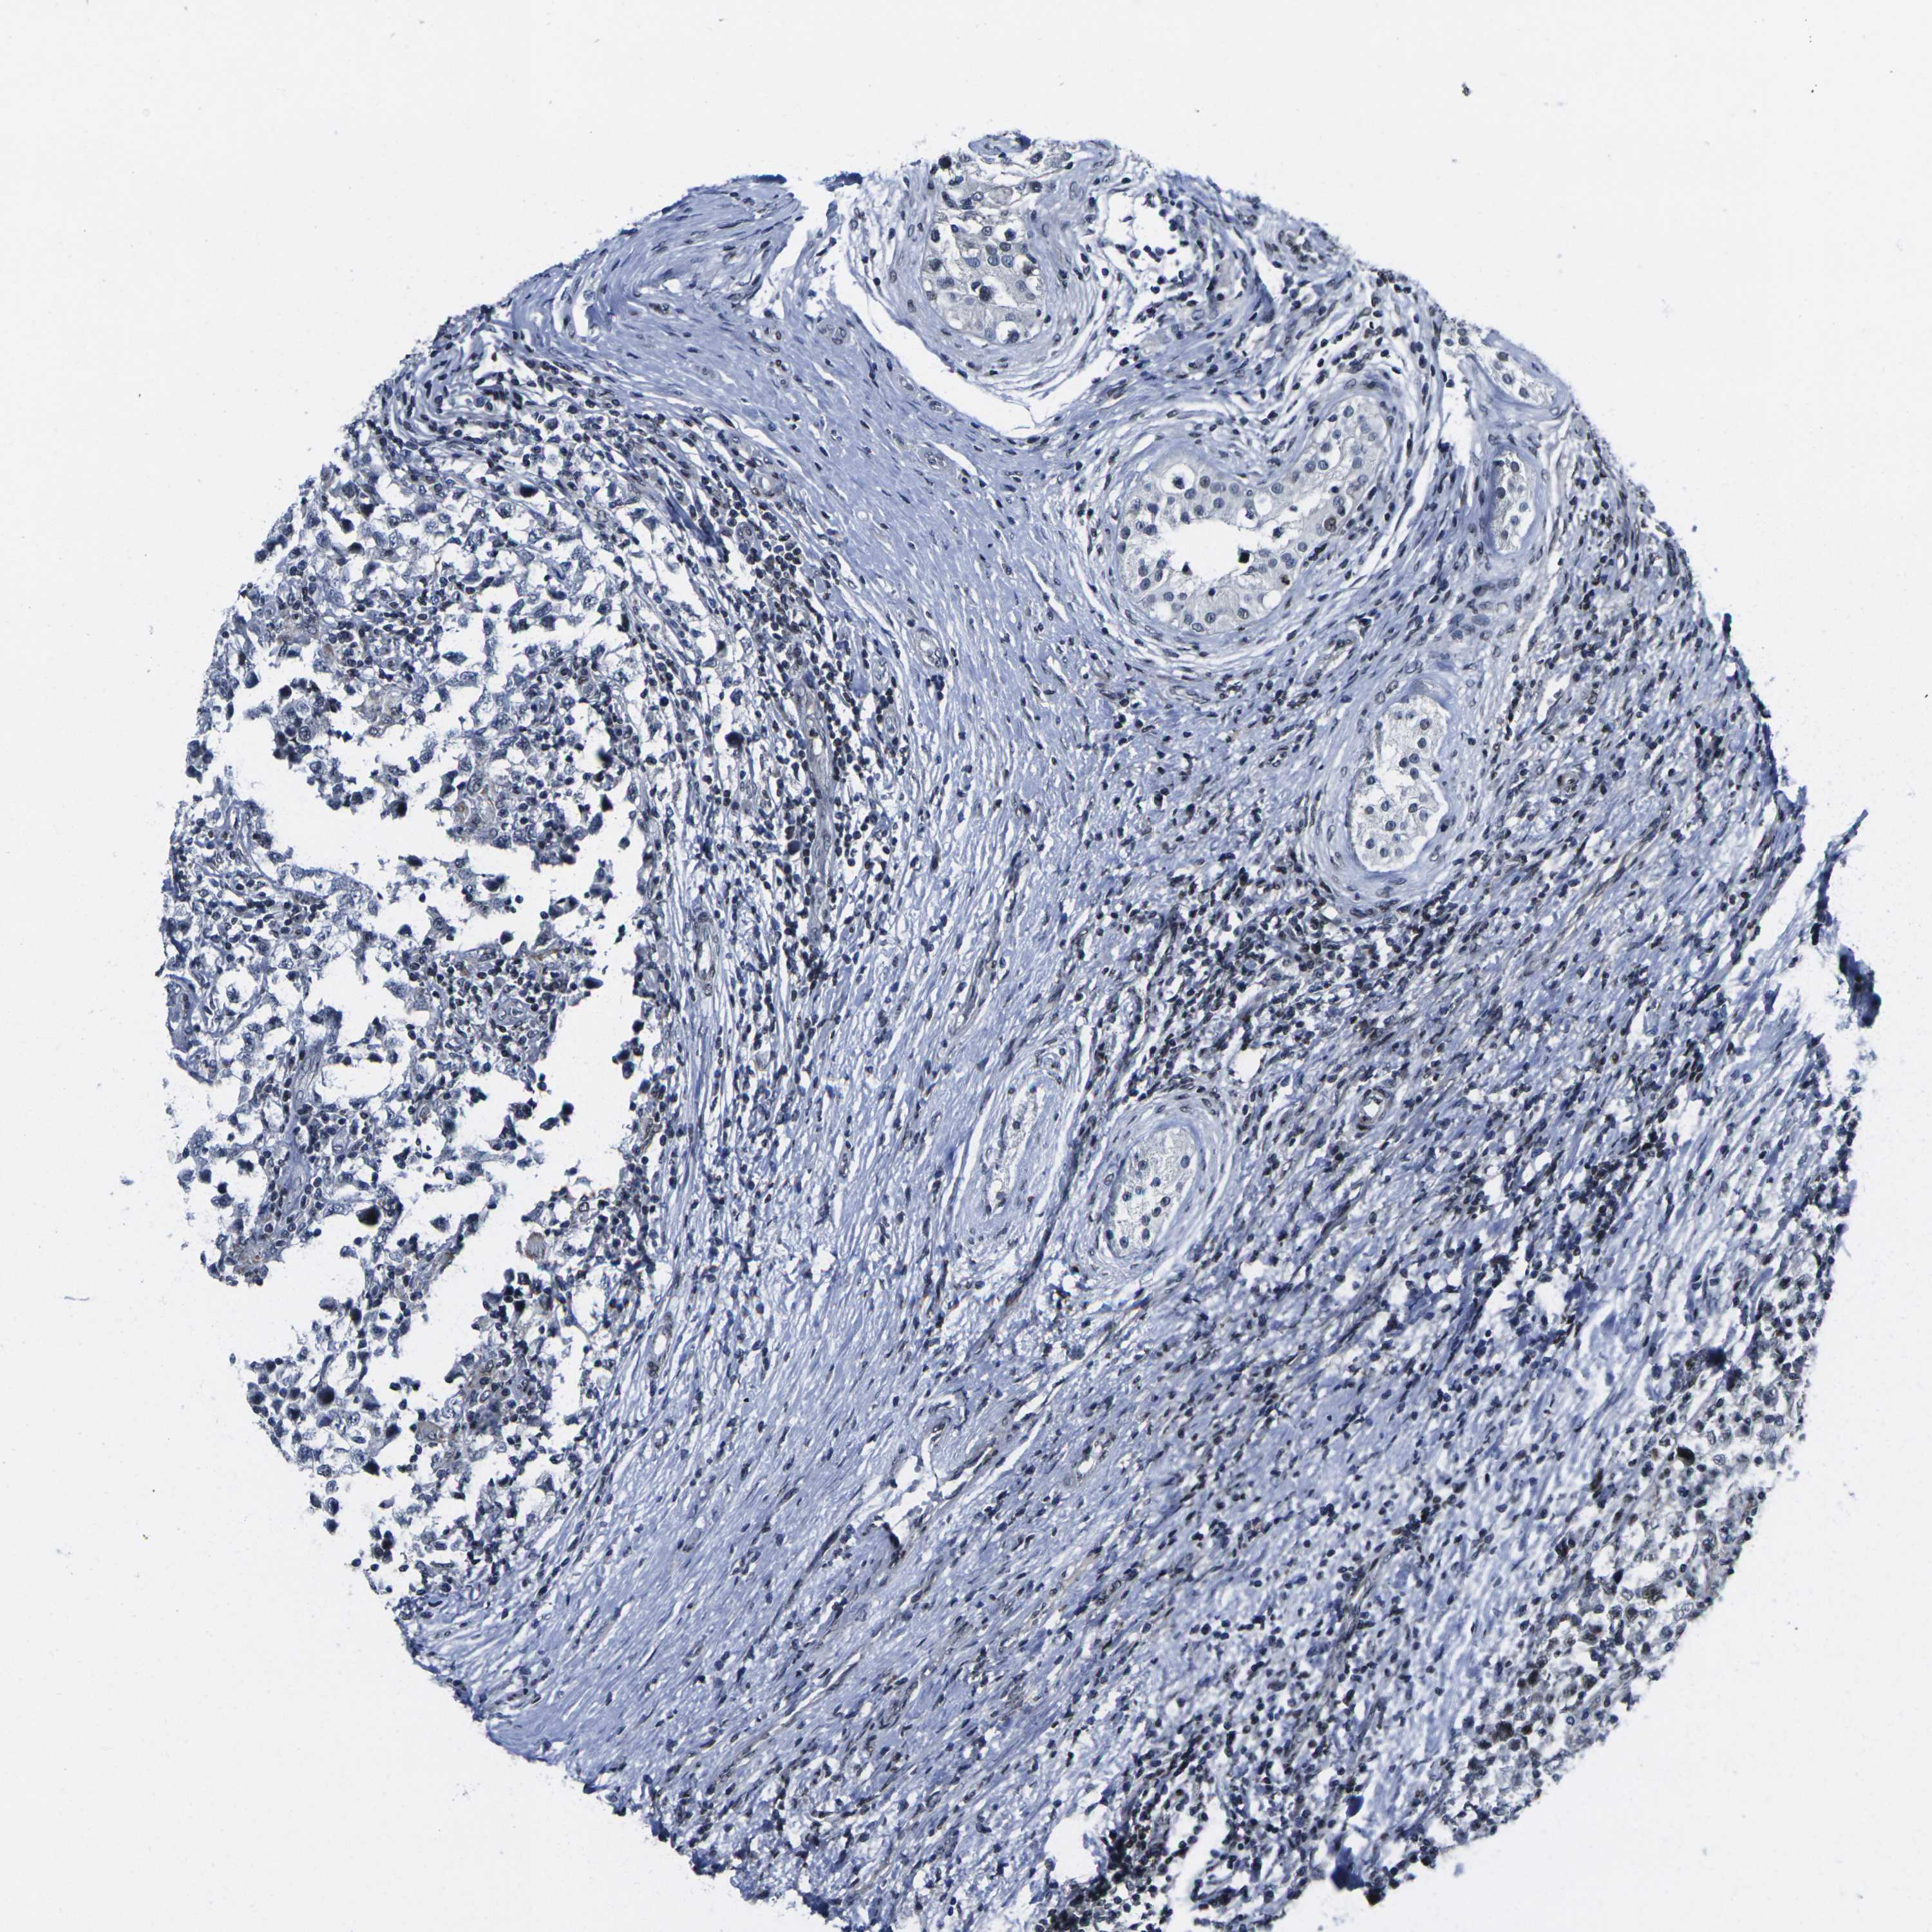

TESTIS CANCER - Protein expressioni

A mouse-over function shows sample information and annotation data. Click on an image to view it in a full screen mode. Samples can be filtered based on level of antibody staining by selecting one or several of the following categories: high, medium, low and not detected. The assay and annotation is described here.

Note that samples used for immunohistochemistry by the Human Protein Atlas do not correspond to samples in the TCGA dataset.

Antibody stainingi

Antibody staining in the annotated cell types in the current human tissue is reported as not detected, low, medium, or high, based on conventional immunohistochemistry profiling in selected tissues. This score is based on the combination of the staining intensity and fraction of stained cells.

Each image is clickable and will lead to virtual microscopy that enables deeper exploration of all samples and also displays staining intensity scores, fraction scores and subcellular localization as well as patient and tissue information for each sample.

Antibody HPA068431

Antibody CAB012235

Staining

High

Medium

Low

Not detected

Intensity

Strong

Moderate

Weak

Negative

Quantity

>75%

75%-25%

<25%

None

Location

Nuclear

Cytoplasmic/membranous

Cytoplasmic/membranous,nuclear

Seminoma, NOS

Carcinoma, Embryonal, NOS